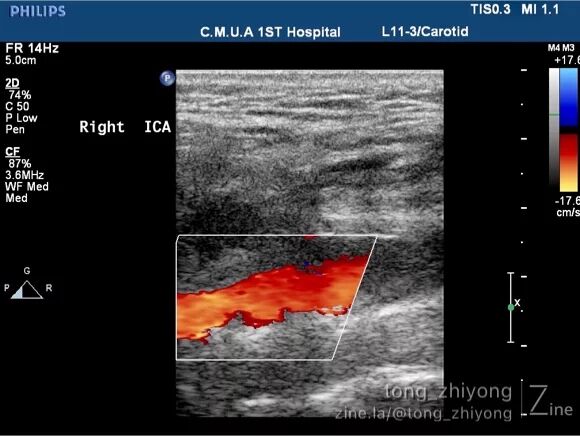

术前颈动脉超声未见斑块内血流信号。

术后一周超声可见:颈总动脉、颈动脉分叉部及颈内动脉近段彩色血流充盈良好,未见明显涡流信号。

术后一周超声可见:颈内动脉近段彩色血流充盈良好,未见涡流。

5. 补片成形术后,“局部的血栓形成”和“局部的涡流”是医生最担心的危险因素。本例CEA补片成形术后的超声证实:局部彩色血流充盈良好,未见涡流和血栓信号;